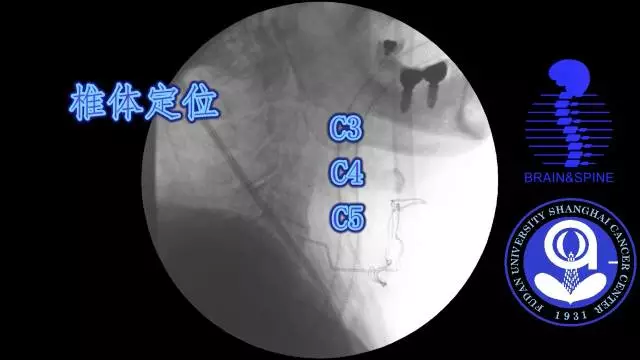

手术过程